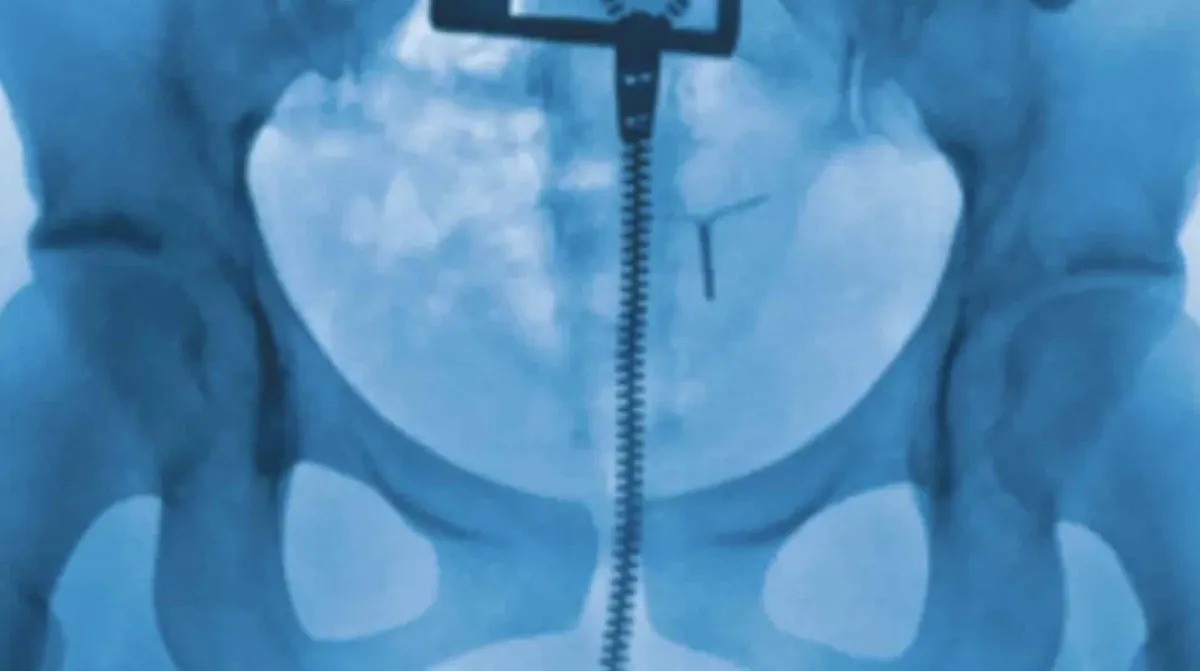

O aguardado retorno da cantora Lorde chegou na sexta-feira, 27 de junho, com o álbum “Virgin”. Após o lançamento de “Solar Power” em 2022, os fãs estavam ansiosos por novas músicas. A capa do álbum, porém, rapidamente roubou a cena e gerou conversas intensas nas redes sociais. Ela não traz o rosto ou o corpo conhecido da artista, mas sim uma imagem científica: um raio-X de uma região pélvica.